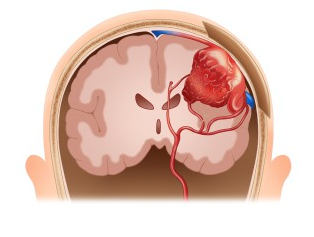

**뇌동정맥기형 (Cerebral Arteriovenous Malformation, AVM)**은 뇌 내의 동맥과 정맥이 비정상적으로 연결된 상태를 의미합니다. 일반적으로 동맥은 산소와 영양분이 풍부한 혈액을 뇌로 공급하고, 정맥은 이 혈액을 심장으로 돌려보냅니다. 하지만 뇌동맥기형에서는 동맥과 정맥이 직접 연결되어 혈액이 제대로 흐르지 않거나 비정상적인 경로로 흐르게 되어 여러 가지 문제를 일으킬 수 있습니다.

**뇌동정맥기형 (Cerebral Arteriovenous Malformation, AVM)**은 뇌에 있는 동맥과 정맥이 비정상적으로 연결된 혈관 기형을 의미합니다. 정상적으로는 동맥이 산소와 영양분이 풍부한 혈액을 뇌로 공급하고, 정맥은 이 혈액을 심장으로 돌려보내야 합니다. 하지만 뇌동맥기형에서는 동맥과 정맥이 직접적으로 연결되어 혈액이 정상적인 경로로 흐르지 않고, 비정상적인 혈류가 발생하게 됩니다.

이 비정상적인 혈관 구조는 고압 상태를 만들어 혈관 벽에 높은 압력을 가하고, 이로 인해 혈관이 파열되거나 뇌출혈이 발생할 수 있는 위험을 높입니다. 뇌동맥기형은 대부분 선천적으로 발생하며, 주로 뇌의 특정 부위(대뇌 반구, 뇌간 등)에 형성됩니다. 이러한 상태는 뇌혈관의 구조적 결함으로, 혈액 흐름에 장애를 일으키고 뇌출혈, 발작, 신경학적 문제를 유발할 수 있습니다.